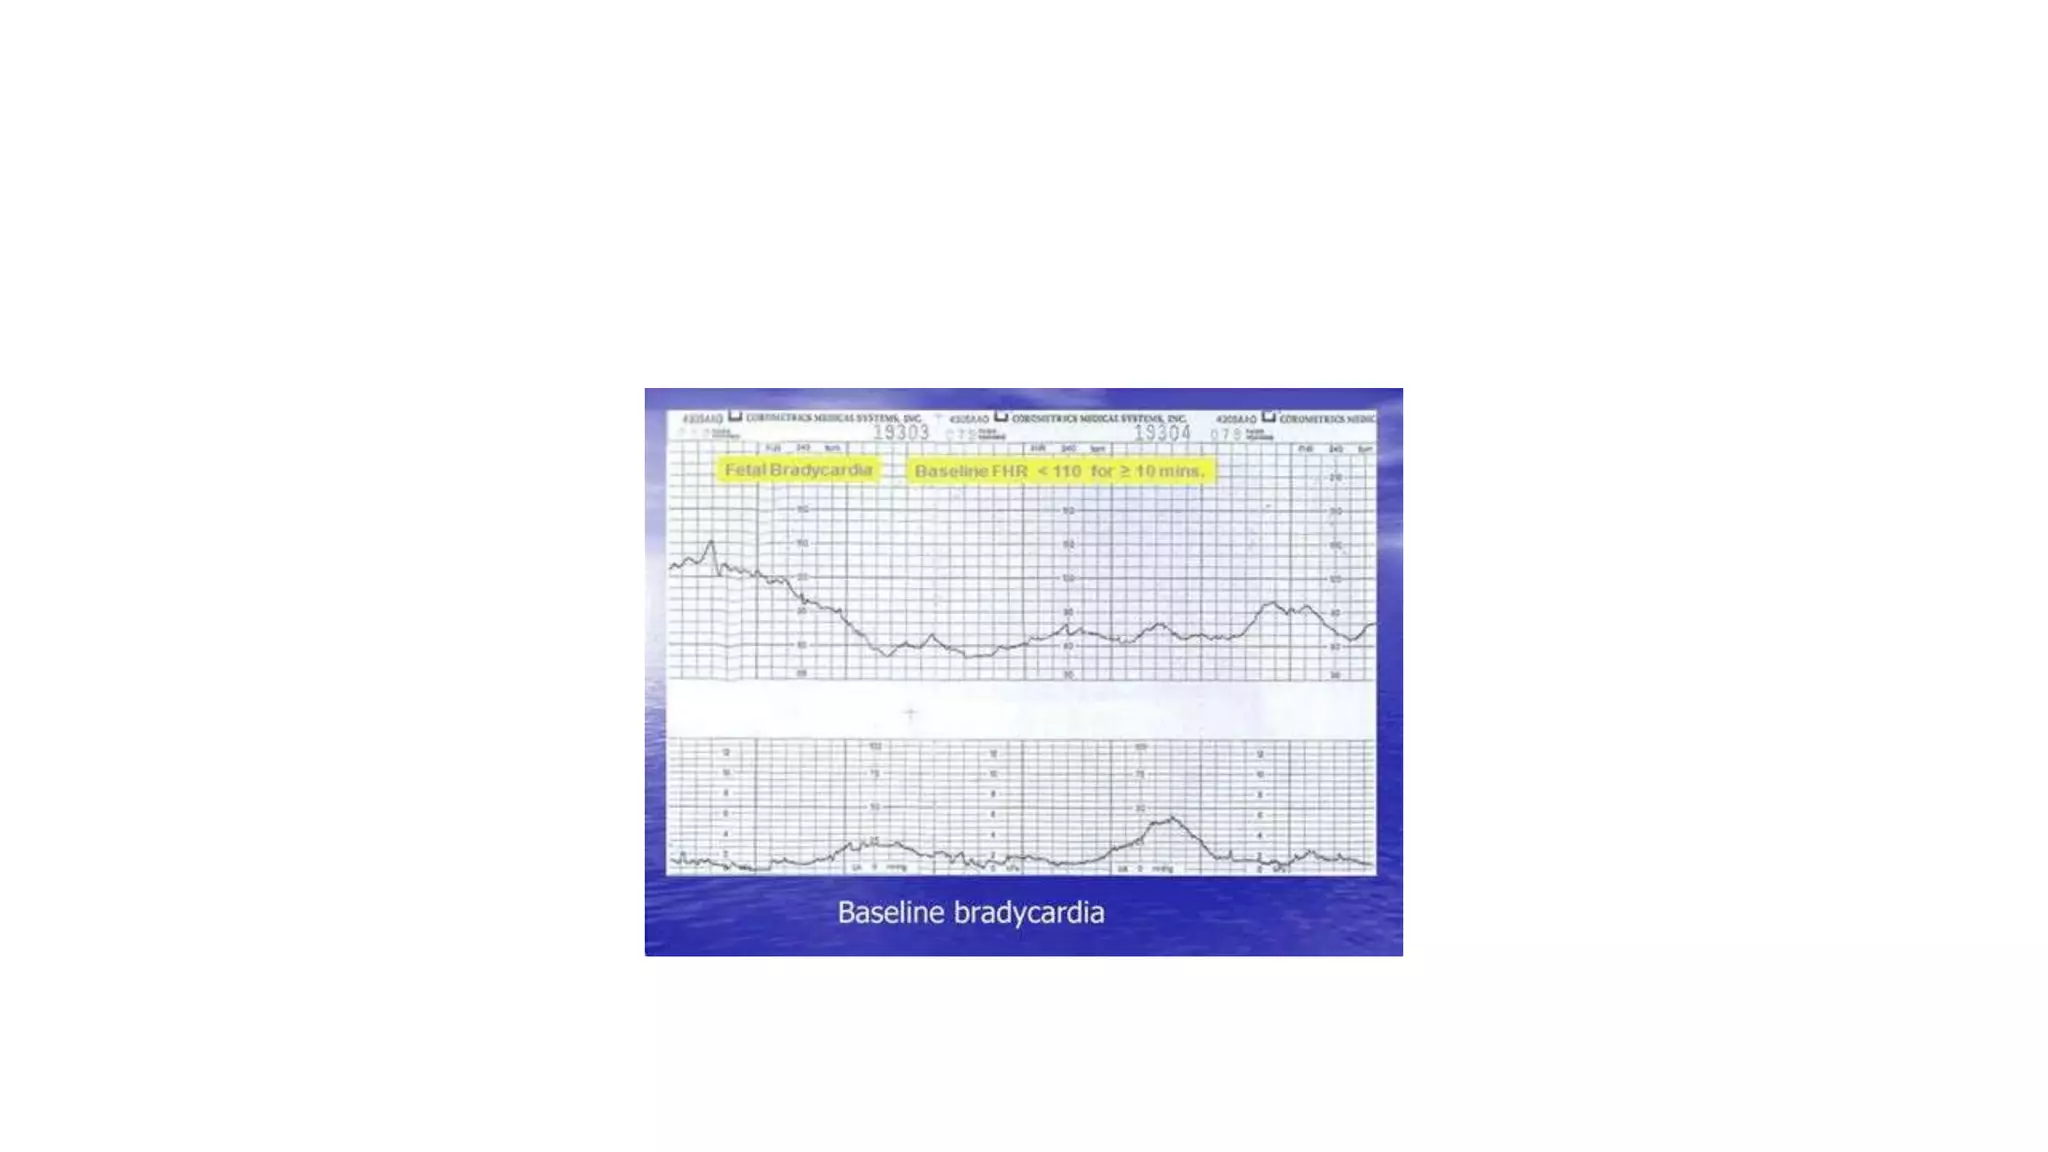

The document discusses key metrics for monitoring a baby's heart rate in utero, including the normal baseline rate of 100-160 bpm and variability. It also covers types of accelerations and decelerations that can occur, such as early or late, as well as bradycardia, which is an abnormally slow heart rate.